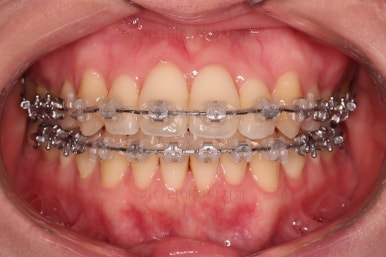

1년 2개월이라는 비교적 짧은 기간안에 원하시는 부분을 깔끔하게 개선했습니다.

전후 비교해 볼게요.

이번 환자분도 삐뚤한 치열을 비발치로,심지어 미니스크류 사용도 없었고 치간삭제도 거의 하지 않았는데요.

입이 나오거나 뻐뜨러지는 느낌 전혀 없죠?

진료 메카니즘을 잘 구성하고 철사를 잘 다뤄주면 좋은 결과를 얻을 수 있답니다.

이상 비발치로 덧니를 개선한 치료사례였습니다.